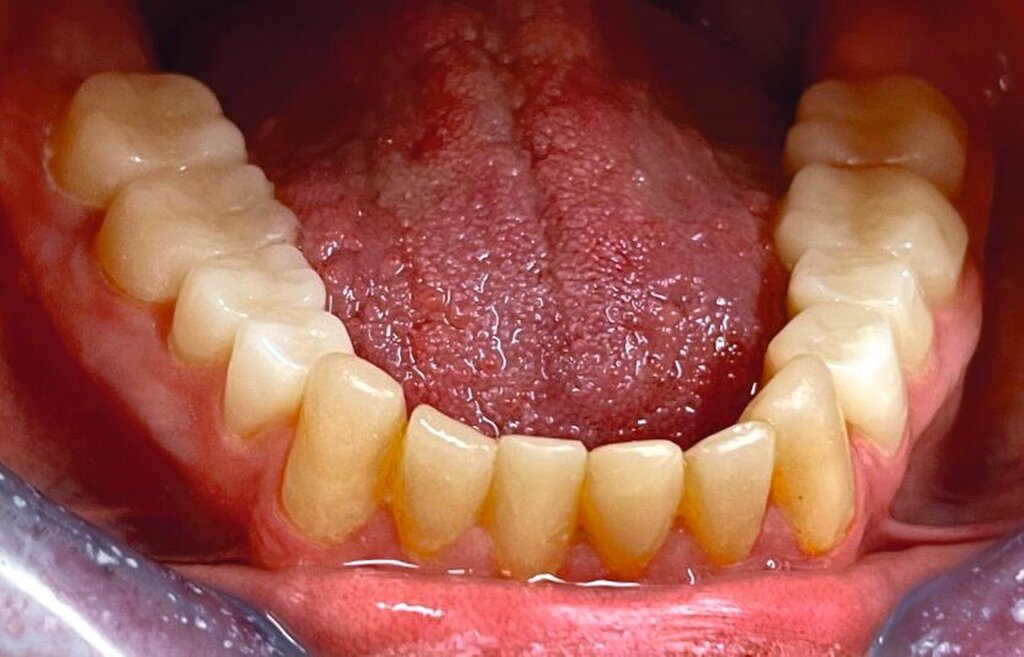

Die zu diesem Zeitpunkt seit fünf Jahren inserierten Frontzahnkronen zeigten Randverfärbungen sowie durch den Durchbruch entstandene Stufen zur natürlichen Zahnhartsubstanz (Abbildung 9). Diese wurden durch Sandstrahlen (CoJet, Solventum), anschließende Konditionierung mit einem Drei-Schritt-Etch-and-Rinse-System und Komposit (Filtek Supreme, Solventum; Tetric EvoFlow, Ivoclar Vivadent) korrigiert und abschließend poliert.